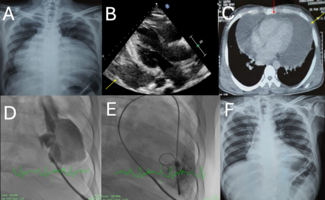

A 41-year-old man with unrepairable pulmonary atresia with ventricular septal defect presented with new onset dyspnea.

A 35-year-old man with human immunodeficiency virus/acquired immunodeficiency syndrome (HIV/AIDS) and a CD4 count of 61 cells per mm3 (normal range: 500-1200 cells/mm3) presented with worsening shortness of breath and orthopnoea over the...